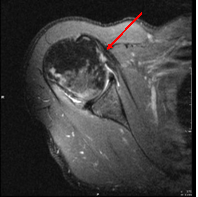

Supscapularis tendon rupture

Ruptured tendon